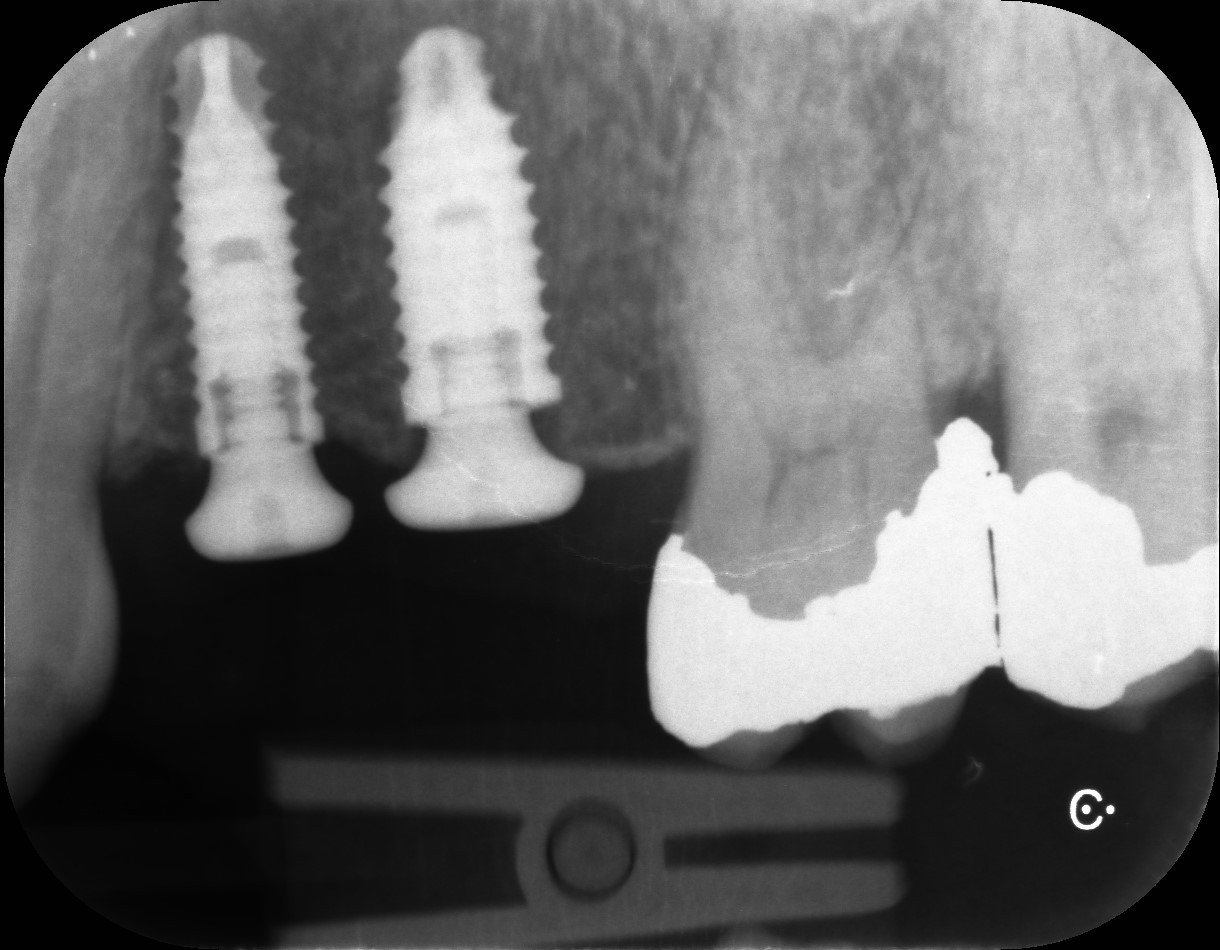

Examples of our work.

Multiple Teeth case with Sinus Lift